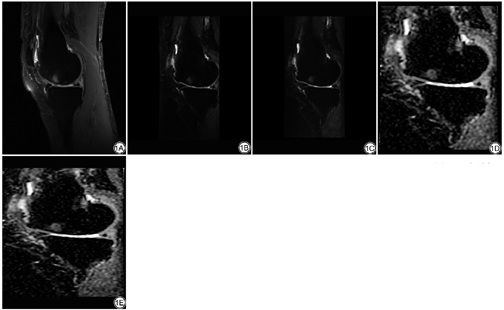

膝关节MRI示骨髓水肿灶呈絮状、小点片状、斑片状异常信号,主要为扩散性不规则或地图形,边界均不清晰,PDWI-FS、DWI均呈高信号(图1)。fFOV DWI ADC图骨髓水肿类型见图2;fFOV DWI ADC图检出的180个病灶中,Ⅰ型32个,Ⅱ型43个,Ⅲ型105个。rFOV DWI ADC图检出179个病灶中,Ⅰ型31个,Ⅱ型43个,Ⅲ型105个。